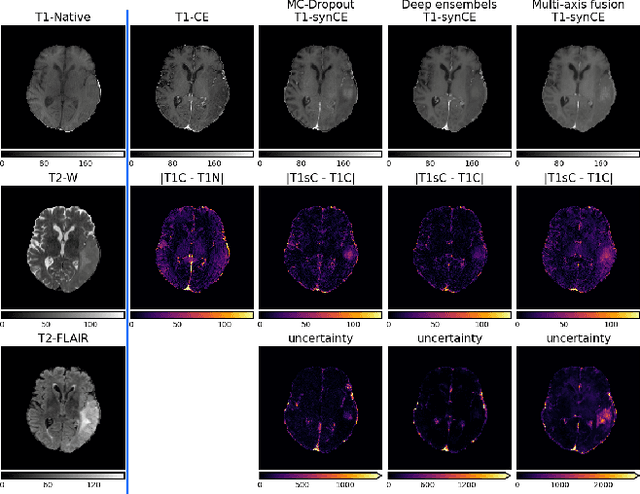

In recent years, deep learning has been applied to a wide range of medical imaging and image processing tasks. In this work, we focus on the estimation of epistemic uncertainty for 3D medical image-to-image translation. We propose a novel model uncertainty quantification method, Multi-Axis Fusion (MAF), which relies on the integration of complementary information derived from multiple views on volumetric image data. The proposed approach is applied to the task of synthesizing contrast enhanced T1-weighted images based on native T1, T2 and T2-FLAIR scans. The quantitative findings indicate a strong correlation ($\rho_{\text healthy} = 0.89$) between the mean absolute image synthetization error and the mean uncertainty score for our MAF method. Hence, we consider MAF as a promising approach to solve the highly relevant task of detecting synthetization failures at inference time.